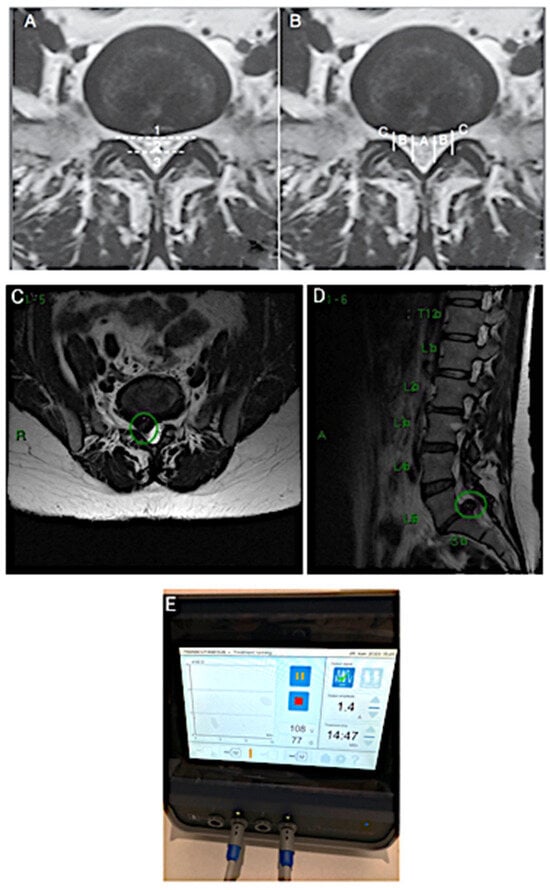

2. CASE 1: Lumbar Root Pain

4. CASE 3: Lumbar Disc with Compression and Central Stenosis